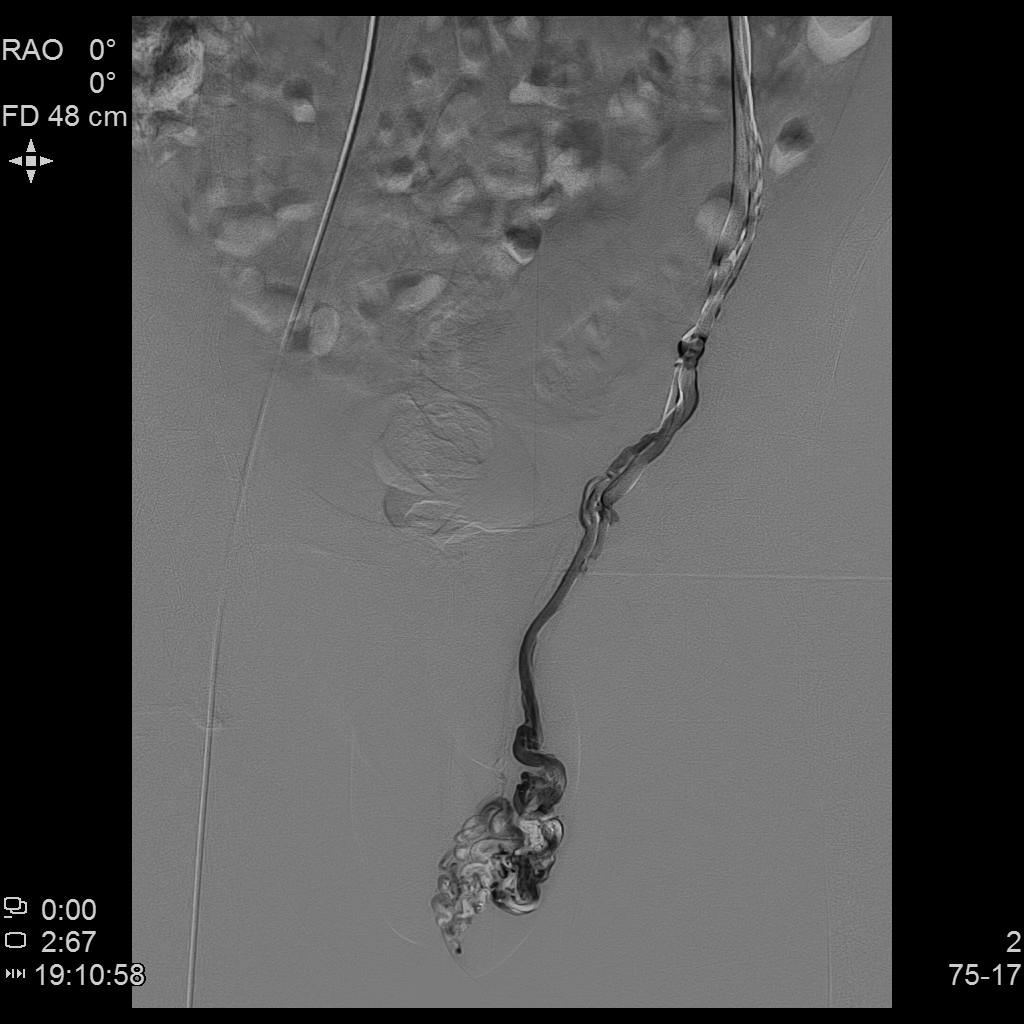

- 行左侧精索静脉造影显示左侧精索静脉明显扩张、迂曲,血流逆流。予以超选插管至左侧精索静脉中下段行弹簧圈栓塞+泡沫硬化栓塞治疗。复查造影显示左侧精索静脉主干闭塞。

左侧精索静脉造影2